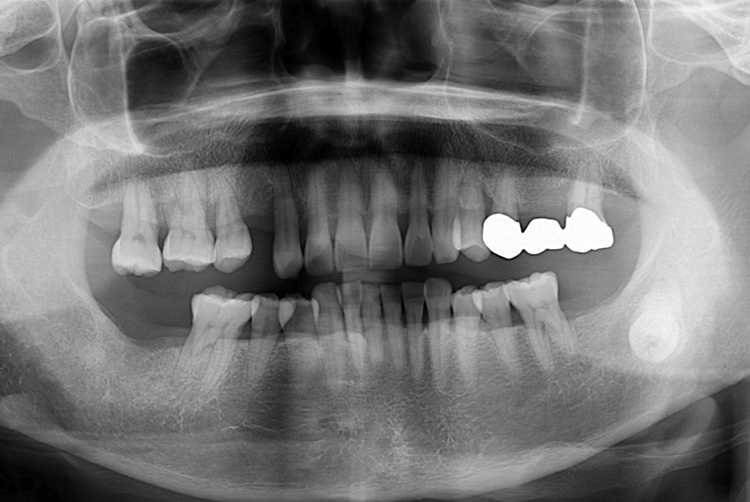

치료사례

세종치과의 진심 어린 치료는 결과로 말합니다.

실제 내원하신 환자분들의 치료 전·후 사례를 확인해보세요.

모든 치료사례 전후사진은 환자분의 동의하에 촬영되었습니다.

모든사진은 동일 환자분의 전후모습을 촬영하였으며, 사진의 밝기조절 외에 임의 수정이 없음을 알려드립니다.